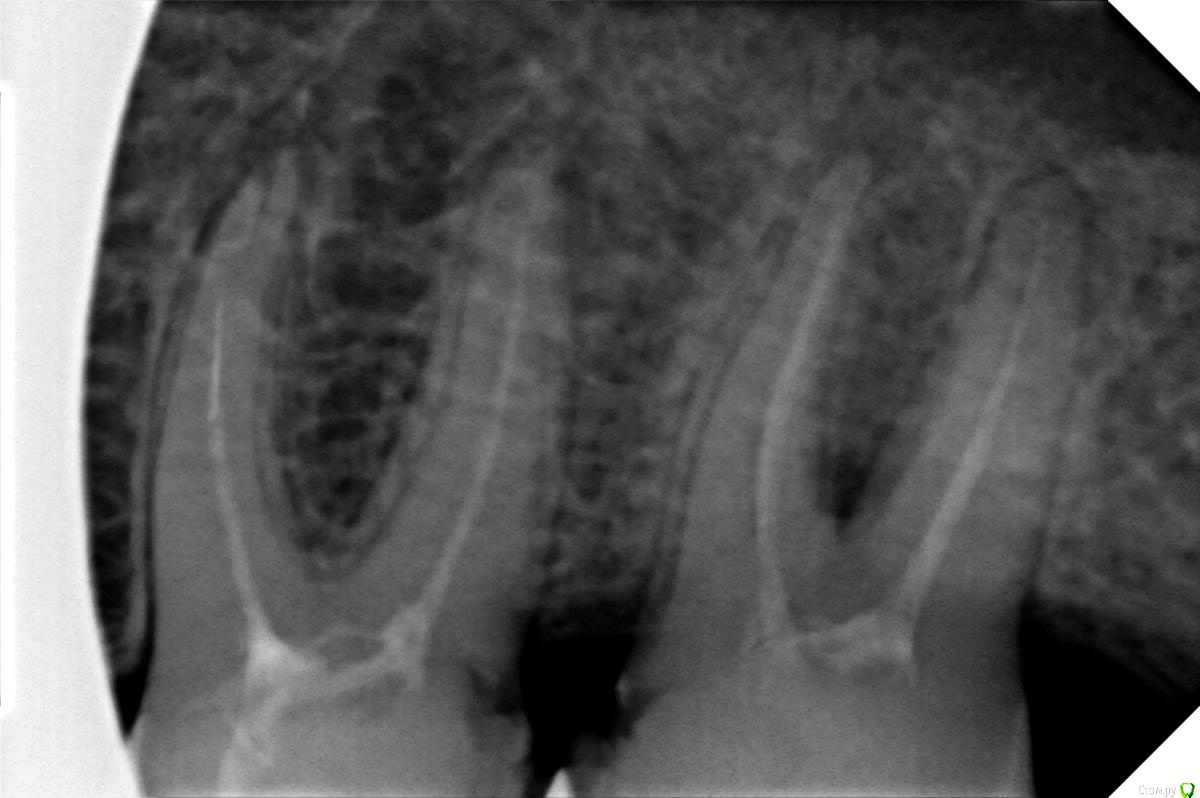

Vlad7772 Опубликовано 11 августа, 2019 Автор Поделиться Опубликовано 11 августа, 2019 Спасибо большое за ответ, сделал рентген, так же сделал и КТ, сходил к эндодонтисту, есть воспаление, предложили перелечить каналы, я согласился. Думаю стоит попробовать, зуб не хочу терять.Вопрос в следующем, так получается что ближайшее время когда можно начать процесс это 1 сентября, то доктор занят, то у меня нет возможности,можно ли со свищем на десне дотянуть до этой даты? В принципе, кроме как эстетически он мне не мешает, не болит, но все же там гной и не хочется осложнений. Или поискать другого специалиста с которым получится раньше начать?Спасибо всем.Так же приложу снимок свежего рентгена. Ссылка на комментарий